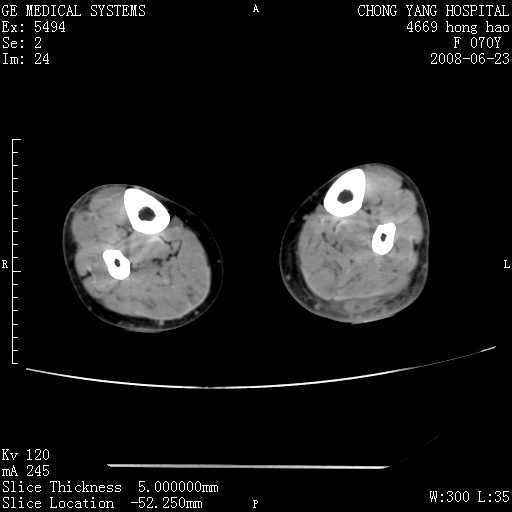

以下是引用zsl6918在2008-6-24 23:07:00的发言:[br]皮下脂肪影模糊,密度增高,但未见具体肿物影,考虑蜂窝组织炎可能性大。

以下是引用zjzjr在2008-6-24 21:44:00的发言:[br]皮下软组织肿厚,脂肪间隙混浊,考虑感染.

以下是引用peijunlong在2008-6-24 20:56:00的发言:[br]左小腿后方软组织皮下脂肪间隙见条片状密度增高影,范围较大,相邻皮下见条索影。[br]考虑:无菌性炎症可能性大[br]鉴别:主要与蔓状血管瘤鉴别,蔓状血管瘤也可表现为软组织内葡伏生长的扁平状的软组织密度影,但它的范围更大,且主要在软组织内,肌间隙中,皮下脂肪间隙内罕见。